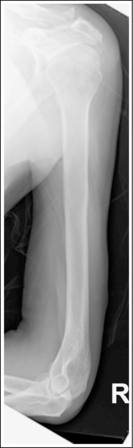

See Figures 4-86 and 4-87 and Box 4-22.

The humerus is in an AP projection. The medial and lateral humeral epicondyles are demonstrated in profile, and the radial head and tuberosity are superimposed over the lateral aspect of the proximal ulna by approximately 0.25 inch (0.6 cm). The greater tubercle is demonstrated in profile laterally, the humeral head is demonstrated medially in profile, and the vertical cortical margin of the lesser tubercle is visible approximately halfway between the greater tubercle and the humeral head.

• An AP projection is obtained by placing the patient in a supine or upright AP projection, with the affected arm extended. Supinate the hand and externally rotate the elbow until an imaginary line drawn between the palpable humeral epicondyles is aligned parallel with the IR (Figure 4-88). This positioning places the proximal radius anterior to the ulna, causing the radial head and tuberosity to be superimposed over the lateral ulna by approximately 0.25 inch (0.6 cm), and places the greater tuberosity in profile.

• Detecting humeral rotation. Rotation of the humerus is a result of poor humeral epicondyle positioning. When the humeral epicondyles and the greater tuberosity are not demonstrated in profile, measure the amount of radial head and tuberosity superimposition of the ulna to determine how the patient should be repositioned. If less than 0.25 inch (0.6 cm) of the radial head and tuberosity are superimposed over the ulna, the elbow and humerus have been excessively externally rotated (see Image 100). If more than 0.25 inch (0.6 cm) of the radial head and tubercle are superimposed over the ulna, the elbow and humerus have been internally rotated (see Image 101).